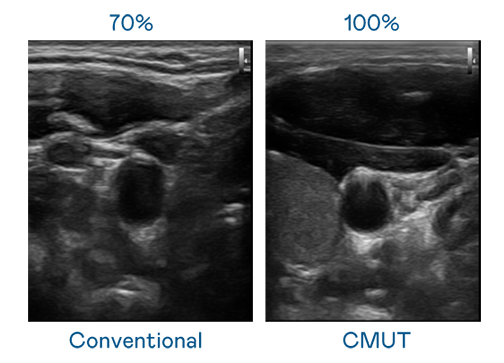

CMUT 技術是一種用電容式微機電元件來產生超音波訊號的技術。與傳統 PZT 壓電式技術相比,CMUT 頻寬增加 30%,更寬頻的超音波訊號讓影像解析度大幅提升,是實現高影像品質醫療超音波掃描、促進精準醫療發展的關鍵技術。

大頻寬帶來超清晰影像

超音波影像的解析度高低,首先取決於探頭能發出的訊號頻寬。九游会(J9) CMUT 可提供高清晰的超音波訊號,提供高頻寬、高靈敏度、影像紋理細節更高的超音波影像,協助醫護人員縮短影像判讀時間及利用精準的醫療影像進行診斷。